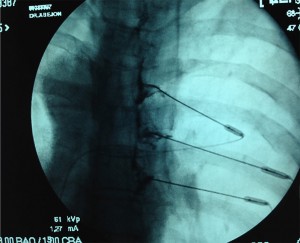

Abordaje posterior retrocrural clásico.

Con el paciente en decúbito prono se coloca una almohada bajo el abdomen. Puntos de referencia con el arco de fluoroscopia en AP se traza un triangulo cuya base está a nivel de L3-L4 con 7.5cm a cada lado y el vértice en la apófisis espinosa de L1. Las agujas se introducen a ambos vértices de la base del triangulo con angulación de 45º en dirección craneal hasta hacer contacto con el cuerpo vertebral de L1, después se aumenta la inclinación hasta 60º para atravesar tangencialmente el cuerpo vertebral hasta llegar al borde anterior del mismo, comprobándolo con el arco de fluoroscopia en lateral. Se inyecta contraste radiopaco (5ml) para ver la localización y difusión del contraste.